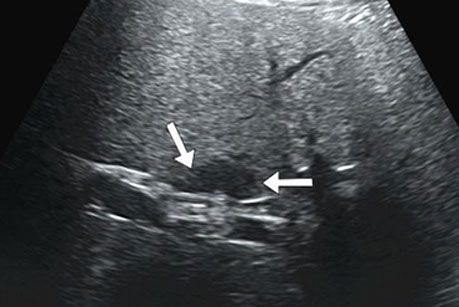

在超声造影检查前,二维超声检查可见患者肝左内叶胆囊旁低回声结节,大小为2.0cm×1.1cm,形态稍欠规则,边界清,结节内部未见明显血流。经患者左侧肘部静脉注入超声造影剂后,发现肝内结节与周围肝实质三期同步增强,考虑结节为良性病变,肝内结节是由于肝内脂肪沉积不均所致。检查过程持续10 分钟,造影结束后留观 15 分钟,患者无不良反应后拔出静脉穿刺针,检查结束。得知自己肝内结节考虑是良性病变,只需定期复查时,压在王先生心里的一块大石头终于落地了。

肝内新发片状低回声结节,二维图像上难以判断良恶性

通过造影剂,可实时动态观察结节内部的微循环血流灌注情况,做出诊断